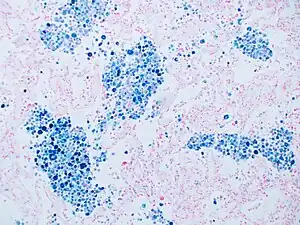

Stain for iron

Prussian blue is a common histopathology stain used by pathologists to detect the presence of iron in biopsy specimens, such as in bone marrow samples. The original stain formula, known historically (1867) as "Perls Prussian blue" after its inventor, German pathologist Max Perls (1843–1881), used separate solutions of potassium ferrocyanide and acid to stain tissue (these are now used combined, just before staining). Iron deposits in tissue then form the purple Prussian blue dye in place, and are visualized as blue or purple deposits.[39]

Histopathology of the liver, showing a Kupffer cells with significant hemosiderin deposition next to a hepatocyte with lipofuscin pigment. H&E stain.

Prussian blue staining, highlighting the hemosiderin pigment as blue.

Prussian blue stain